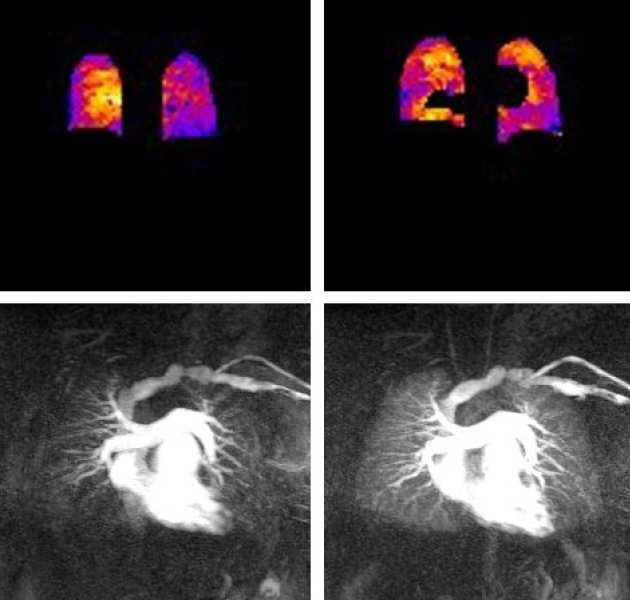

We are investigating the use of oxygen-enhanced MRI ventilation mapping in combination with MR perfusion to provide increased diagnostic accuracy when compared with ventilation-perfusion SPECT scintigraphy in patients with pulmonary hypertension.

A novel deep learning-based and ROI focused multi-scale super-resolution approach is proposed to improve the apparent spatial resolution of in vivo Diffusion Tensor Cardiovascular Magnetic Resonance (DT-CMR).